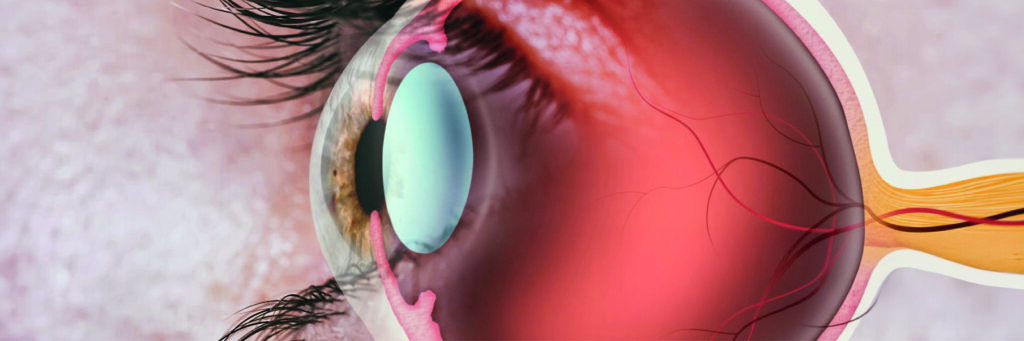

A retina é uma das estruturas mais importantes do olho humano e desempenha um papel fundamental para a visão. Trata-se de uma fina camada de tecido sensível à luz localizada na parte interna e posterior do globo ocular. Ela atua como um “filme fotográfico” biológico, captando a luz e transformando-a em sinais elétricos que serão interpretados pelo cérebro.

Quando a luz atravessa a córnea, a pupila e o cristalino, ela atinge a retina, onde é convertida em sinais elétricos. Esses sinais viajam pelo nervo óptico até o cérebro, que forma a imagem final.

Camadas da Retina

A retina possui múltiplas camadas, cada uma com funções específicas:

- Epitélio Pigmentar da Retina (EPR): nutre as células fotorreceptoras.

- Camada de Fotorreceptores: responsável pela captação da luz.

- Camadas Intermediárias: processam e transmitem informações visuais.

- Camada de Células Ganglionares: envia sinais para o nervo óptico.